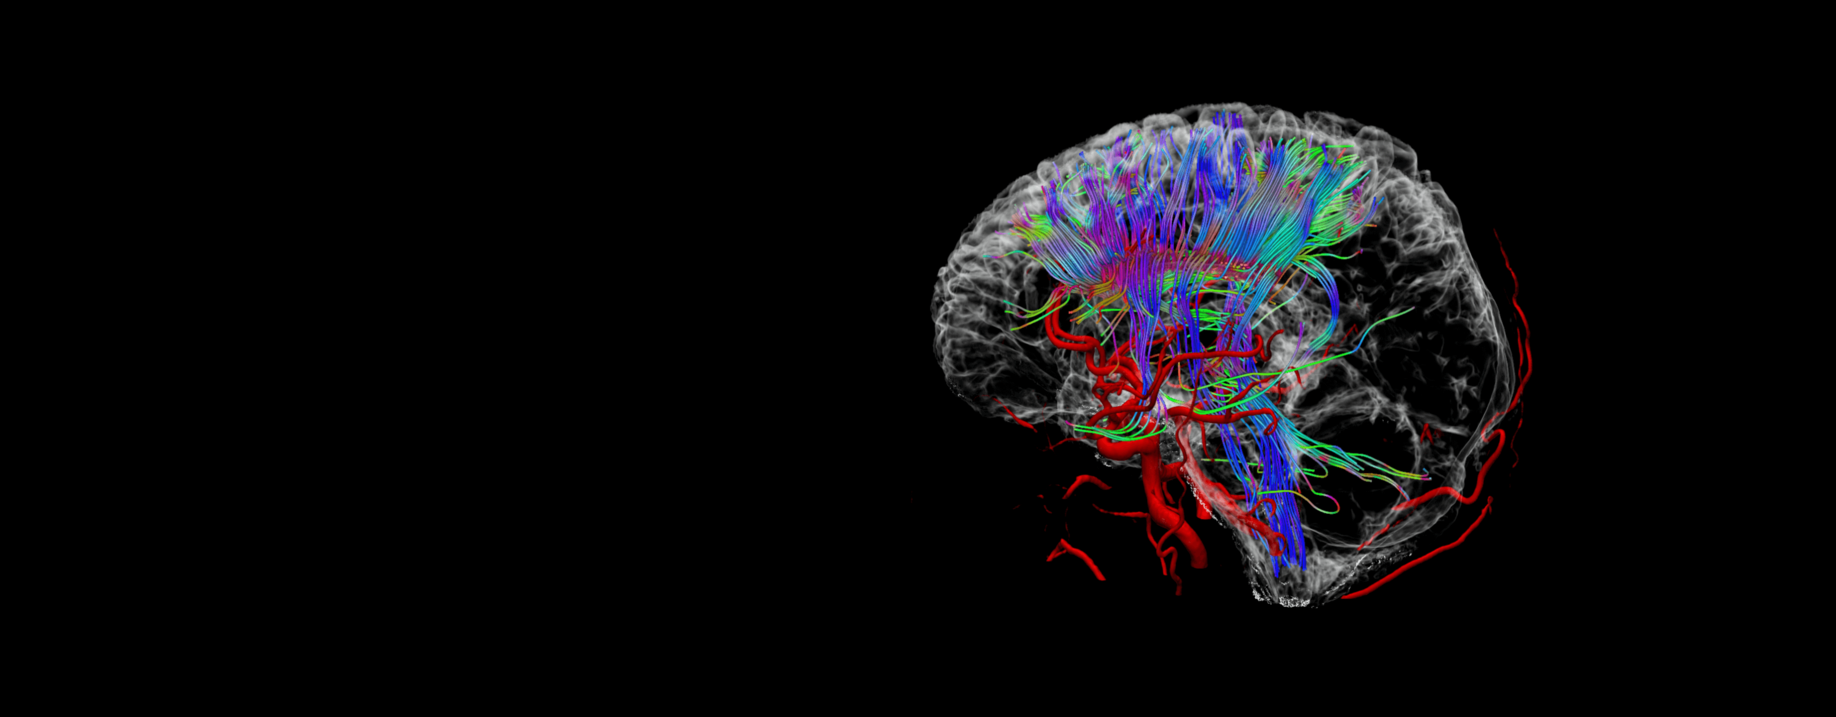

MR联合神经分析

用于分析神经磁共振BOLD(血氧水平依赖)和DTI(扩散张量成像)数据。提供融合功能,更直观的观察感兴趣区中激活区,纤维束,病灶和血管等相互之间的关系。